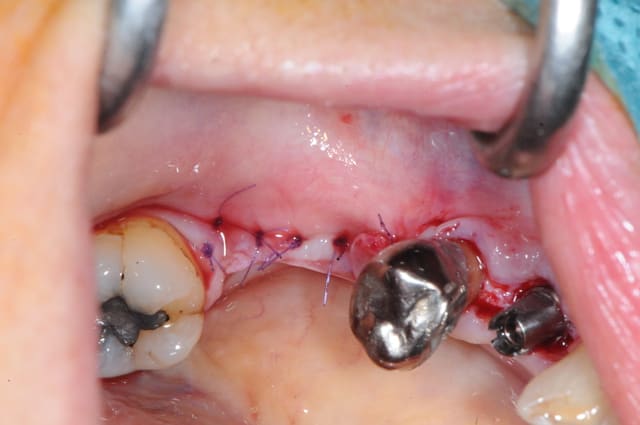

voici la dernière greffe en BioBank faite avec les greffons corticaux que j'ai réalisé il y a 10 jours.

10 sutures en u

Dsc 2786 hqdc5l - Eugenol